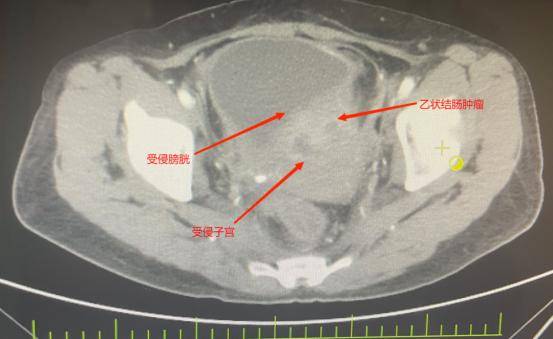

邹女士被确诊为乙状结肠癌,肿瘤已“疯狂”侵犯膀胱、子宫、输尿管等多个盆腔脏器,还伴随不全性肠梗阻。2个月前在外院住院治疗,因手术风险大,外院仅为她做了横结肠造口术缓解梗阻,可术后不幸出现结肠膀胱瘘——小便中混着大便的症状让她痛苦不堪,叠加尿路感染、肿瘤引发的消化道出血,以及尿路梗阻导致的肾功能不全,多重并发症叠加,生活质量跌至谷底。

先是完整切除受肿瘤侵犯的直肠与乙状结肠原发灶,紧接着剥离与肿瘤紧密粘连的子宫及双侧附件并完整移除,随后小心翼翼分离膀胱与周围组织,将受侵膀胱全部切除——前三项切除手术已耗极大精力,团队仍需在腹腔镜下用回肠精心构建新的膀胱通路,确保患者术后排尿功能正常。